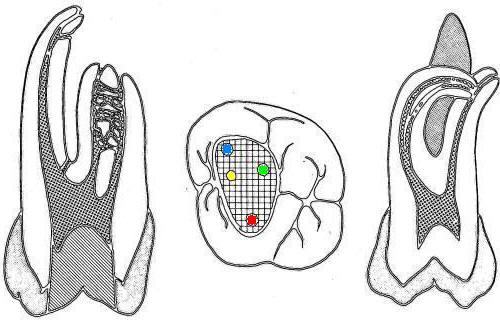

• En azul conducto mesiovetibular

• En verde conducto mesiolingual

• En rojo conducto distal

• En amarillo un cuarto conducto,  si el conducto distal se encuentra desplazado hacia lingual, existe una alta posibilidad de encontrar un cuarto conducto

Similar al primer molar inferior pero menos voluminoso, en la raíz mesial siempre encontrará dos conductos y en la raíz distal puede encontrar uno ó dos conductos.